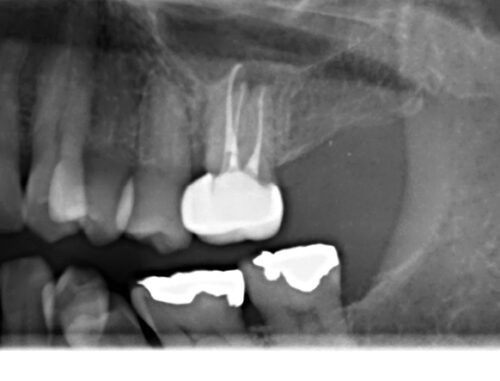

レントゲンを見ると歯は失活歯で口蓋根にメインポイントが1本入っていますが頬側根は手付かずのようです。

取れた詰め物は再利用できなかったので、患者さんには再度根管治療からやり直すことを提案し同意を得ました。根管口付近を慎重に探っていくと頬側根の入り口が見つかりました。

根管内を緊密に根管充填されていることが分かります。またチタンクラウンはエックス線に対して半透過性があるのも特徴です。